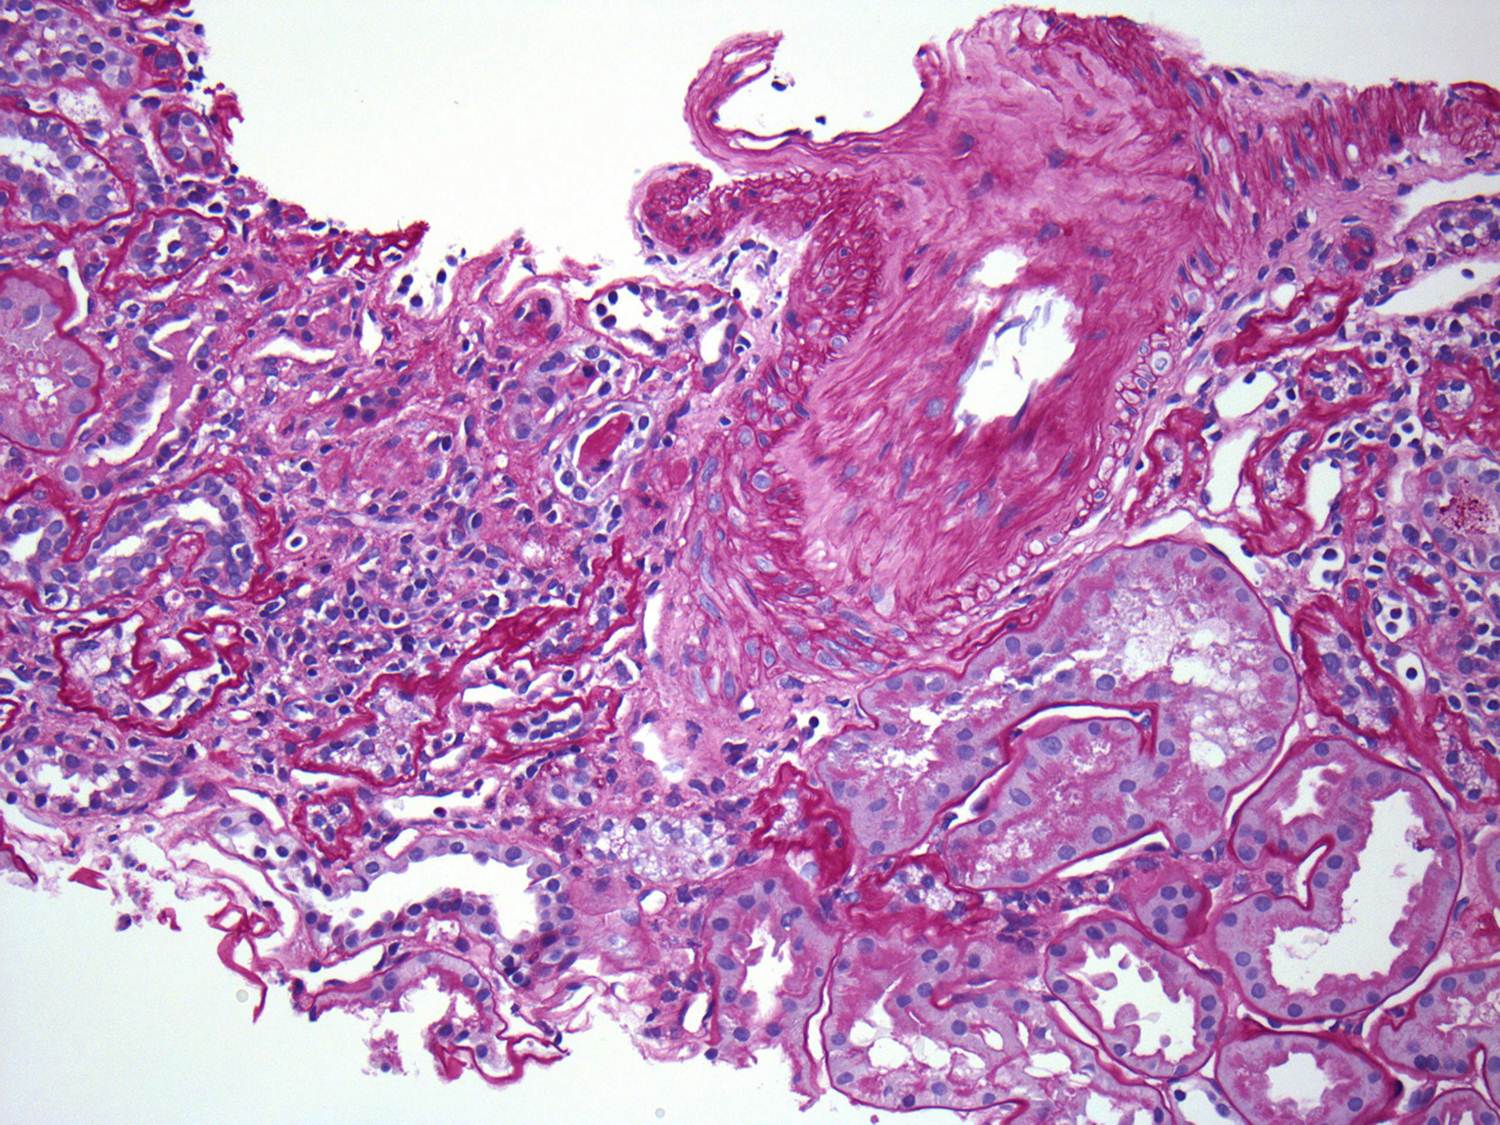

Examination of the renal vasculature revealed severe arterial sclerosis and moderate arteriolar sclerosis.